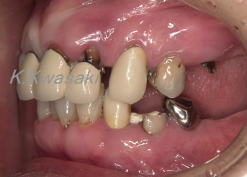

初診時

「全体的に虫歯が多く良く噛めない」と来院されました。

上下奥歯が無く前歯だけで噛んでいるため、前歯が前方に出てきてしまいました。 |

| ほとんどの歯に虫歯があり全体的に歯周病にもなっていました。また口元は前突感があります。全体的な治療が必要な状態です。 |